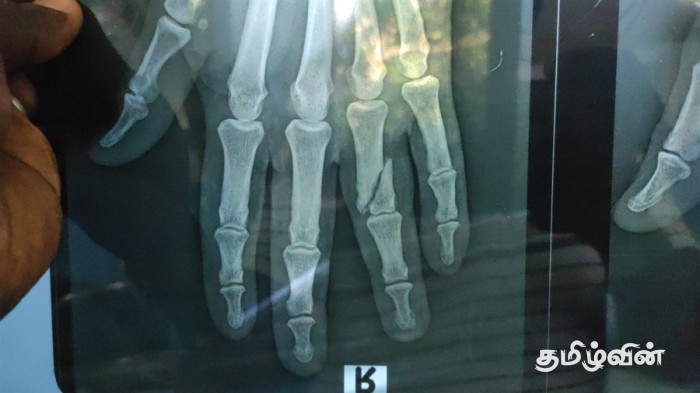

கோம்பாவில் புதுக்குடியிருப்பினை சேர்ந்த 39 அகவையுடைய இரண்டு பிள்ளைகளின் தந்தையே இவ்வாறு கைவிரல் ஒன்று முறிந்த நிலையிலும் காலிலும், கையிலும் கரடியின் கடி காயங்களுக்கு உள்ளான நிலையிலும் முல்லைத்தீவு மாவட்ட மருத்துவமனையில் சிகிச்சைக்காக அனுமதிக்கப்பட்டுள்ளார்.